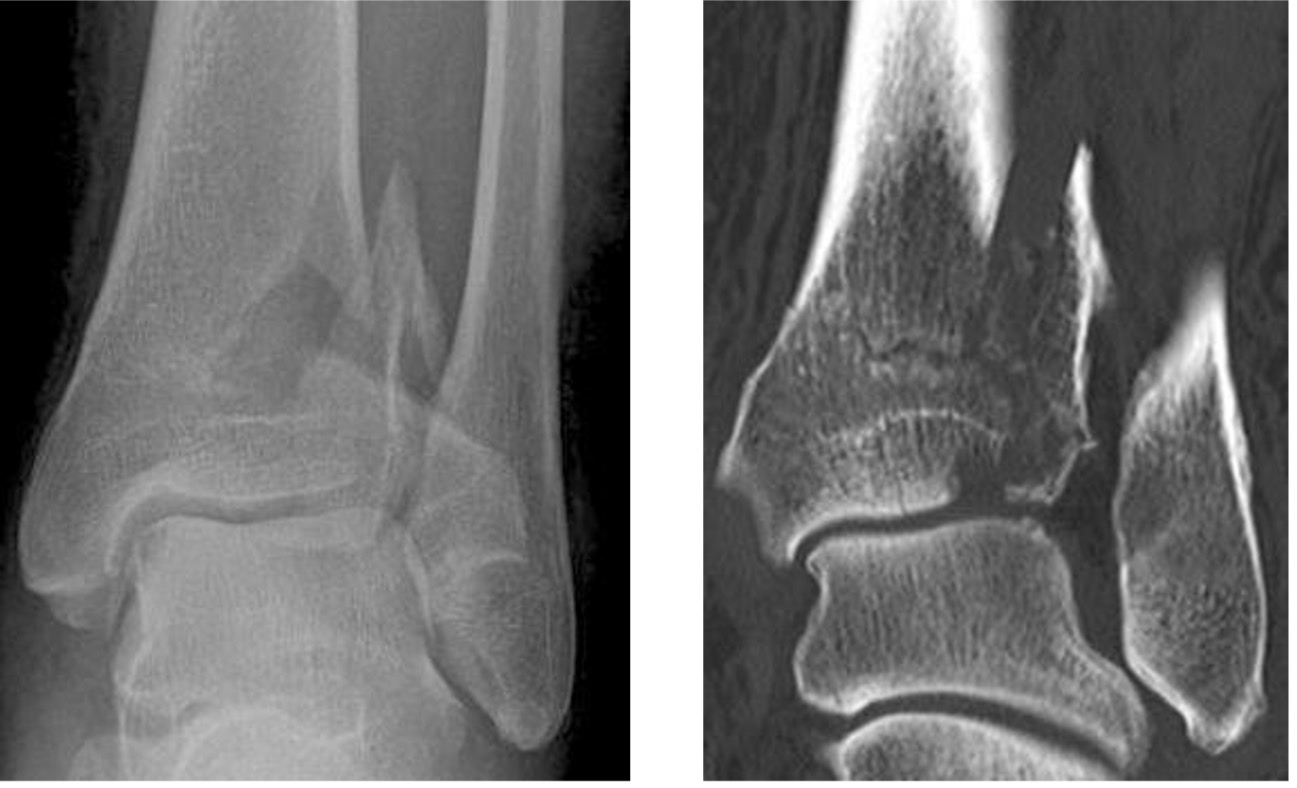

Triplanar fracture

- Salter-Harris type 4 fracture through the lateral distal tibia with sagittal, axial and coronal plane components

- Comprises a vertical fracture through the epiphysis, horizontal fracture through the physis and oblique fracture through the metaphysis

Triplanar fracture extending through the distal tibial epiphysis, physis and metaphysis (arrows)